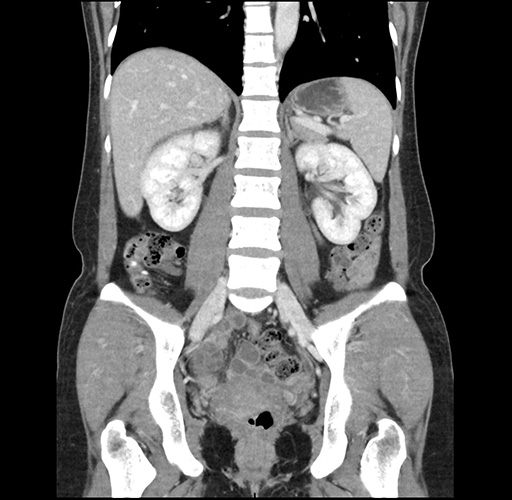

Imaging Analysis

Look through the patient's CT scan to identify any areas of concern for the necessary procedure.

Based on your CT findings, which issue(s) would give reason for "planned slowing down moment(s)" in this case?

Considering a standard left lateral sectionectomy procedure, what step(s) of the operation would you do differently in this case ?